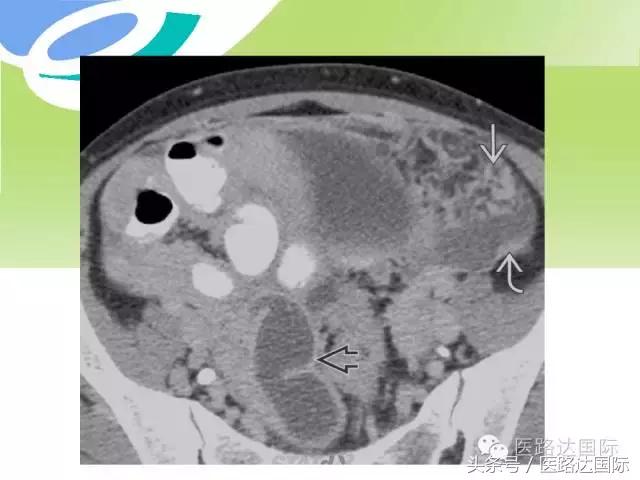

首都医科大学附属北京妇产医院梁宇霆教授从流行病学、临床特点、实验室检查、病理改变、影像学特点及治疗与预后六个方面向我们详细地介绍了女性生殖系统结核;并且着重介绍了子宫输卵管造影(HSG)的作用。在最后,梁教授还向大家介绍了如何鉴别诊断女性生殖系统结核、盆腔炎性病变和卵巢癌。